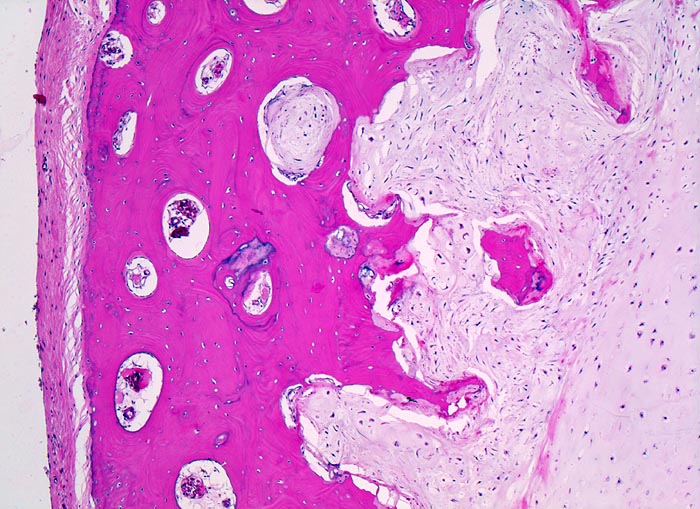

Morphologische Merkmale:

• Von Periost bedeckter kortikaler Knochen.

• Zellarmer lobulierter Knorpeltumor.

• Destruktive Tumorinfiltration des spongiösen und kortikalen Knochens.

• Der maligne Knorpel mit reichlich heller chondroider Matrix gleicht nicht neoplastischem hyalinem Knorpelgewebe.

• Im Vergleich zu normalem Knorpel leicht erhöhte Zellularität.

• In Höhlen liegende Tumorzellen mit hyperchromatischen, leicht vergrösserten Kernen.